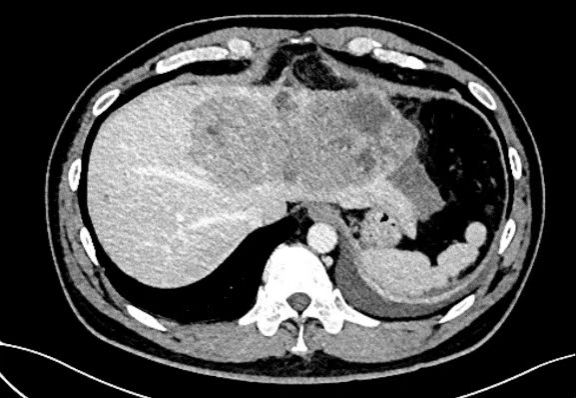

一名四十岁男性患者突发腹痛 1 天由外院转来。患者有慢性乙肝病史,已经多年未做检查,急诊 CT 显示:一个直径约 16 cm×10 cm 的巨大肝癌充满患者左半肝,挤压侵犯第二肝门肝中静脉(图 1,图 2)。更危急的是,肿瘤周围大量积液,怀疑肝癌已发生破裂,患者血压 90/60 mmHg,生命体征岌岌可危。蒋安主任医师接诊后联系输血科董艳迎主任快速输血,迅速纠正休克,使生命体征稳定。